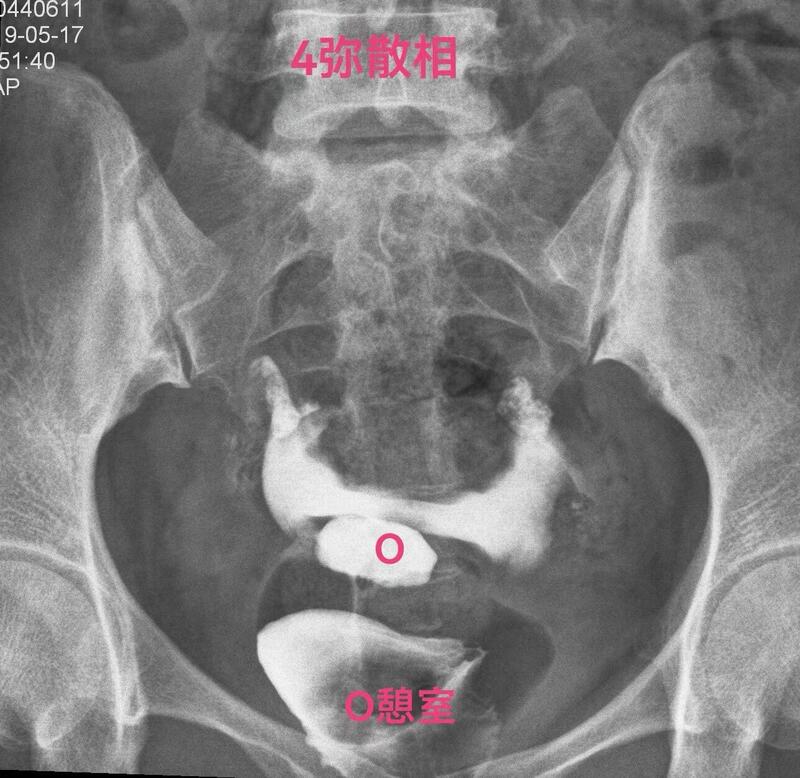

下面一例造影图就可以看直观看懂憩室导致经血流出不畅

3(1).jpg

弥散相子宫腔内造影剂完全流出来了,憩室内还有较多造影剂充满憩室腔。月经血流出相仿。